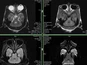

Beyond traditional post-mortem analyses (histology, morphometry, pathophysiological and biochemical markers), non-invasive in vivo imaging techniques are playing an increasingly important role. Prisys Biotech offers advanced in vivo imaging capabilities to longitudinally monitor biological processes in live animals.